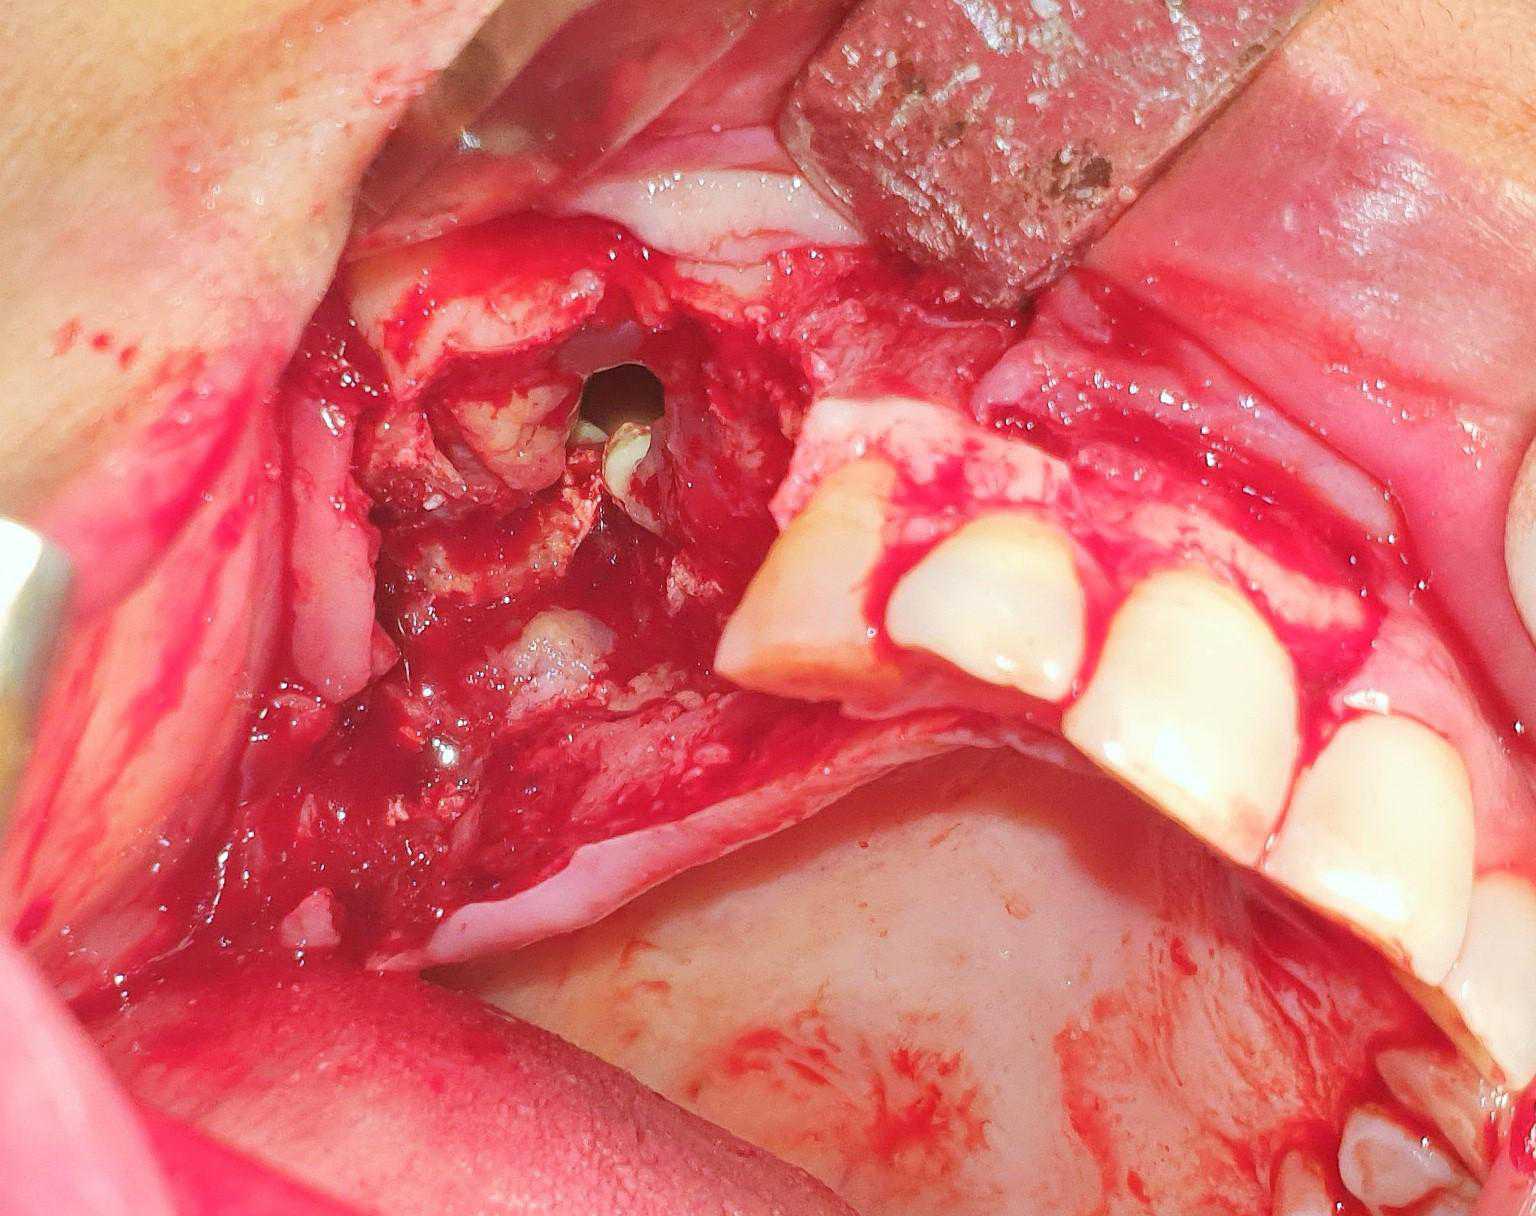

https://demo.discussdentistry.com/forums/topic/post-mucormycosis-avascular-necrosis-of-maxilla-rehabilitation-with-zygomatic/#post-24499 <![CDATA[Post Mucormycosis Avascular necrosis of maxilla, rehabilitation with Zygomatic]]> https://demo.discussdentistry.com/forums/topic/post-mucormycosis-avascular-necrosis-of-maxilla-rehabilitation-with-zygomatic/#post-24499 Thu, 25 Aug 2022 12:14:40 +0000 Sankalp Mittal

• 20210604_101325 (2)20210604_101317 (2)20210604_103315 (2)20210604_102857 (2)20210604_104202 (2)20210604_104853 (2)20210824_105656 (2)20210824_112353 (2)20210824_114957 (2)20210824_131302 (2)20210826_100648 (2)20210826_100749 (2)20210826_100919 (2)20210914_183943 (2)20211001_17535220211012_18543620211012_192043 (2)20211012_185627 (2)20211012_195430 (3)20211027_193725 (2)20211027_200729 (2)20211027_200919